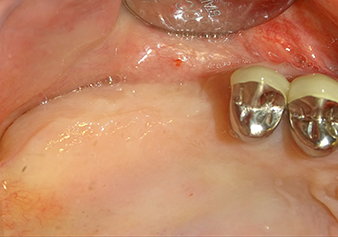

A 49-year-old female patient, a non-smoker and with nothing remarkable in her general medical history, was referred to our oral surgery practice for surgical extraction of tooth 16 and subsequent implantation. After the extraction, the patient experienced mild sinusitis trouble with the resultthat we initially waited six months before carrying out the measure. The residual bone height at the planned implant position measured 3-4 mm (Fig. 1 and 2).

The I2A instrument (diameter 2.0 mm) was then used to perforate the sinus floor intermittently and on the smallest scale possible. This special piezosurgical method ensures that the Schneiderian membrane is not damaged. When the Z25P was used, the membrane was already lifted slightly by the coolant supplied via the instrument tip (Fig. 3). The coolant quantity was just 50% in order to avoid high pressure in the implant bed.